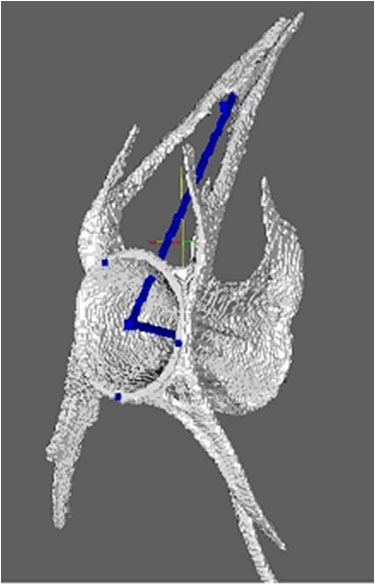

Hand CT to evaluate RA erosions

Additionally we are pursuing several different but related research projects. Methods have been developed and validated to characterize progression the progression of hip and hand OA radiographically (5). In collaboration with Dr. Chris Evans at the Mayo Clinic, Dr. Duryea was recently awarded a supplemental grant to support a study testing the hypothesis that a novel method based on conventional radiography can be used to detect the status of osseous defects with high accuracy. We have also received a NIH grant to support a study to evaluate hand radiography in conjunction with a study of adiposity-related metabolic factors as predictors of incident hand OA. In collaboration with Daniel Solomon in the BWH Rheumatology Division, Department of Medicine we are developing methods to assess hand RA using multi-slice CT. With Drs. Anthony Aliprantis and Matthew Harris, we have initiated a project to apply quantitative methods to assess bone parameters of zebra fish.